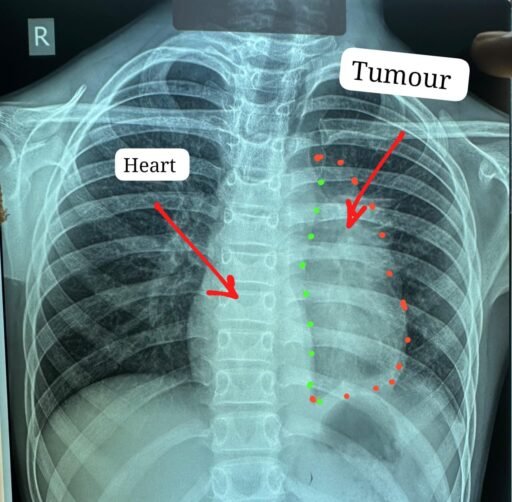

ट्यूमर ने हार्ट के साथ, पेरिकार्डियम, फ्रेनिक नर्व,महाधमनी, मुख्य पल्मोनरी आर्टरी(एमपीए), लेफ्ट एट्रियम एवं फेफड़े को अपनी चपेट में ले रखा था

डॉक्टरों के अनुसार यह ट्यूमर सामान्यतः 40 से 60 वर्ष के लोगों में पाया जाता है और बच्चों में इसका मिलना अत्यंत दुर्लभ है। यह ट्यूमर हृदय, पेरिकार्डियम, फ्रेनिक नर्व महाधमनी (एओर्टा), मुख्य पल्मोनरी आर्टरी, लेफ्ट एट्रियम और फेफड़े से चिपका हुआ था। ऐसे मामलों में ट्यूमर को पूरी तरह निकाल पाना (आर-0 रिसेक्शन) लगभग असंभव माना जाता है, लेकिन अस्पताल में उपलब्ध हार्ट-लंग मशीन की मदद से यह संभव हो पाया।

मुख्य ट्यूमर के अलावा फेफड़े की प्लूरल कैविटी में फैले तीन अन्य सैटेलाइट ट्यूमर को भी सावधानीपूर्वक निकाला गया, ताकि भविष्य में कैंसर दोबारा फैलने की संभावना न रहे। निकाले गए ट्यूमर का आकार लगभग 12×8 सेंटीमीटर और वजन करीब 400 ग्राम था।